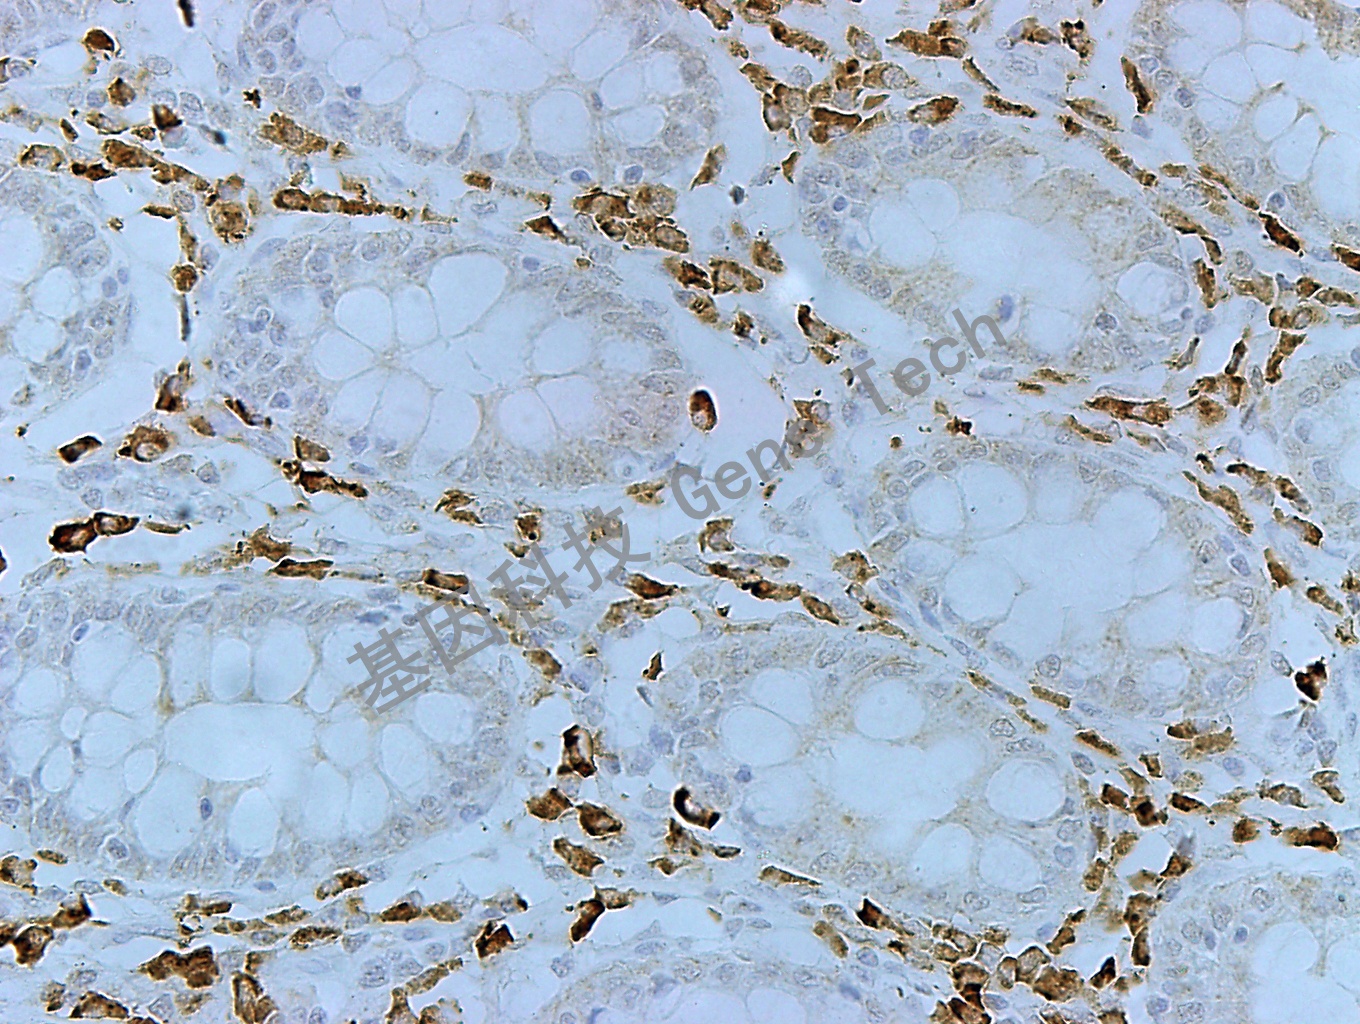

| 結(jié)腸癌石蠟切片,用 MUC-6(GT2220)染色,細(xì)胞漿陽性,DAB 顯色。 | ||

| 預(yù)處理:高pH熱修復(fù) | 陽性部位:細(xì)胞漿 | 陽性對照:胃 |